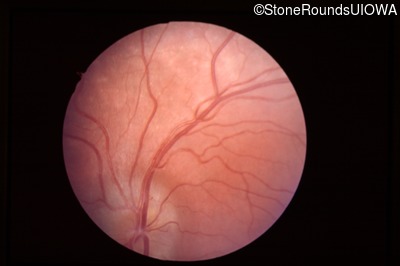

Fundus Photography - Left - 20/40 -2

Exemplar